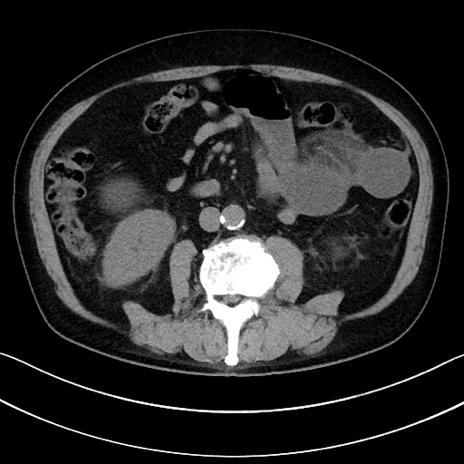

症例15(横断像)

【症例】70歳代男性

【主訴】腹痛

【現病歴】今朝から腹痛あり。全体的に痛い。特に左上の方。排ガスが今日はない。冷や汗が出る。

【既往歴】直腸癌術後

【身体所見】左側腹部〜上腹部に圧痛あり。腹膜刺激症状明らかなではない。軽度反跳痛。左下腹部に術後瘢痕あり。

【データ】WBC 7700、CRP 0.02